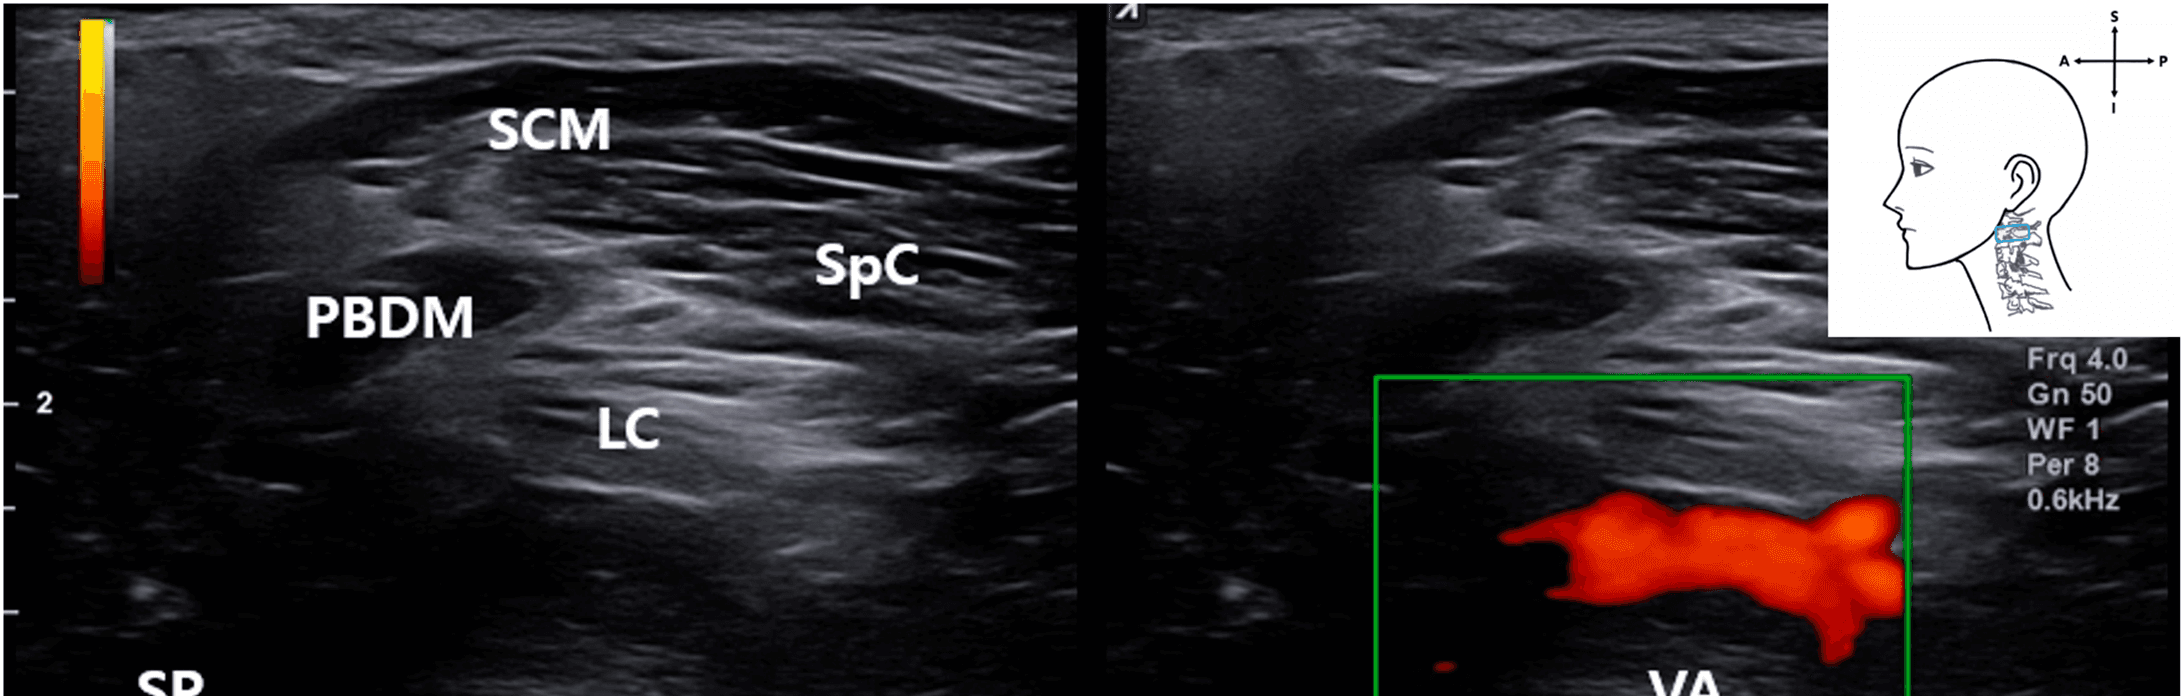

안면마비 - Ultrasound image showing the VA located deep between the posterior belly of the Figure 4. Ultrasound image showing the VA located deep between the posterior belly of the digastric muscle and occipital condyle. The SCM muscle lies superficially. This image was obtained with the probe tilted superiorly using a heel-toe maneuver to visualize the upper cervical region. SCM , sternocleidomastoid muscle; PBDM , posterior belly of digastric muscle; SpC , splenius capitis muscle; VA , vertebral artery; OC , occipital condyle; SP , styloid process; LC , Longissimus capitis muscle); blue rectangle, probe position.

특히 고해상도 초음파로 제1경추 횡돌기와 후궁을 안정적으로 시각화할 수 있었고, 프로브를 상방으로 기울이는 heel-toe 기법을 통해 척추동맥을 상부 경추 부위에서 일관되게 확인할 수 있었습니다.